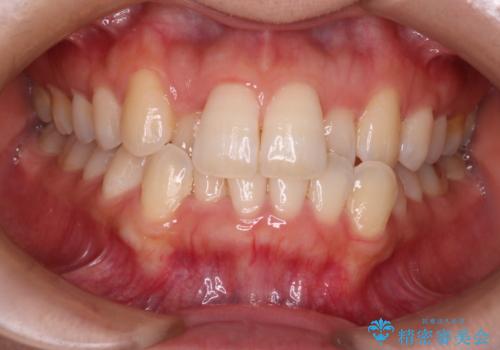

30代女性 前歯のがたつき

![[ 前歯のガタつきを治す ]マウスピース矯正インビザラインの症例 治療前](https://seimitsushinbi.jp/wp/wp-content/uploads/2022/01/IMG_0237-500x350.jpg?v=1642039695)